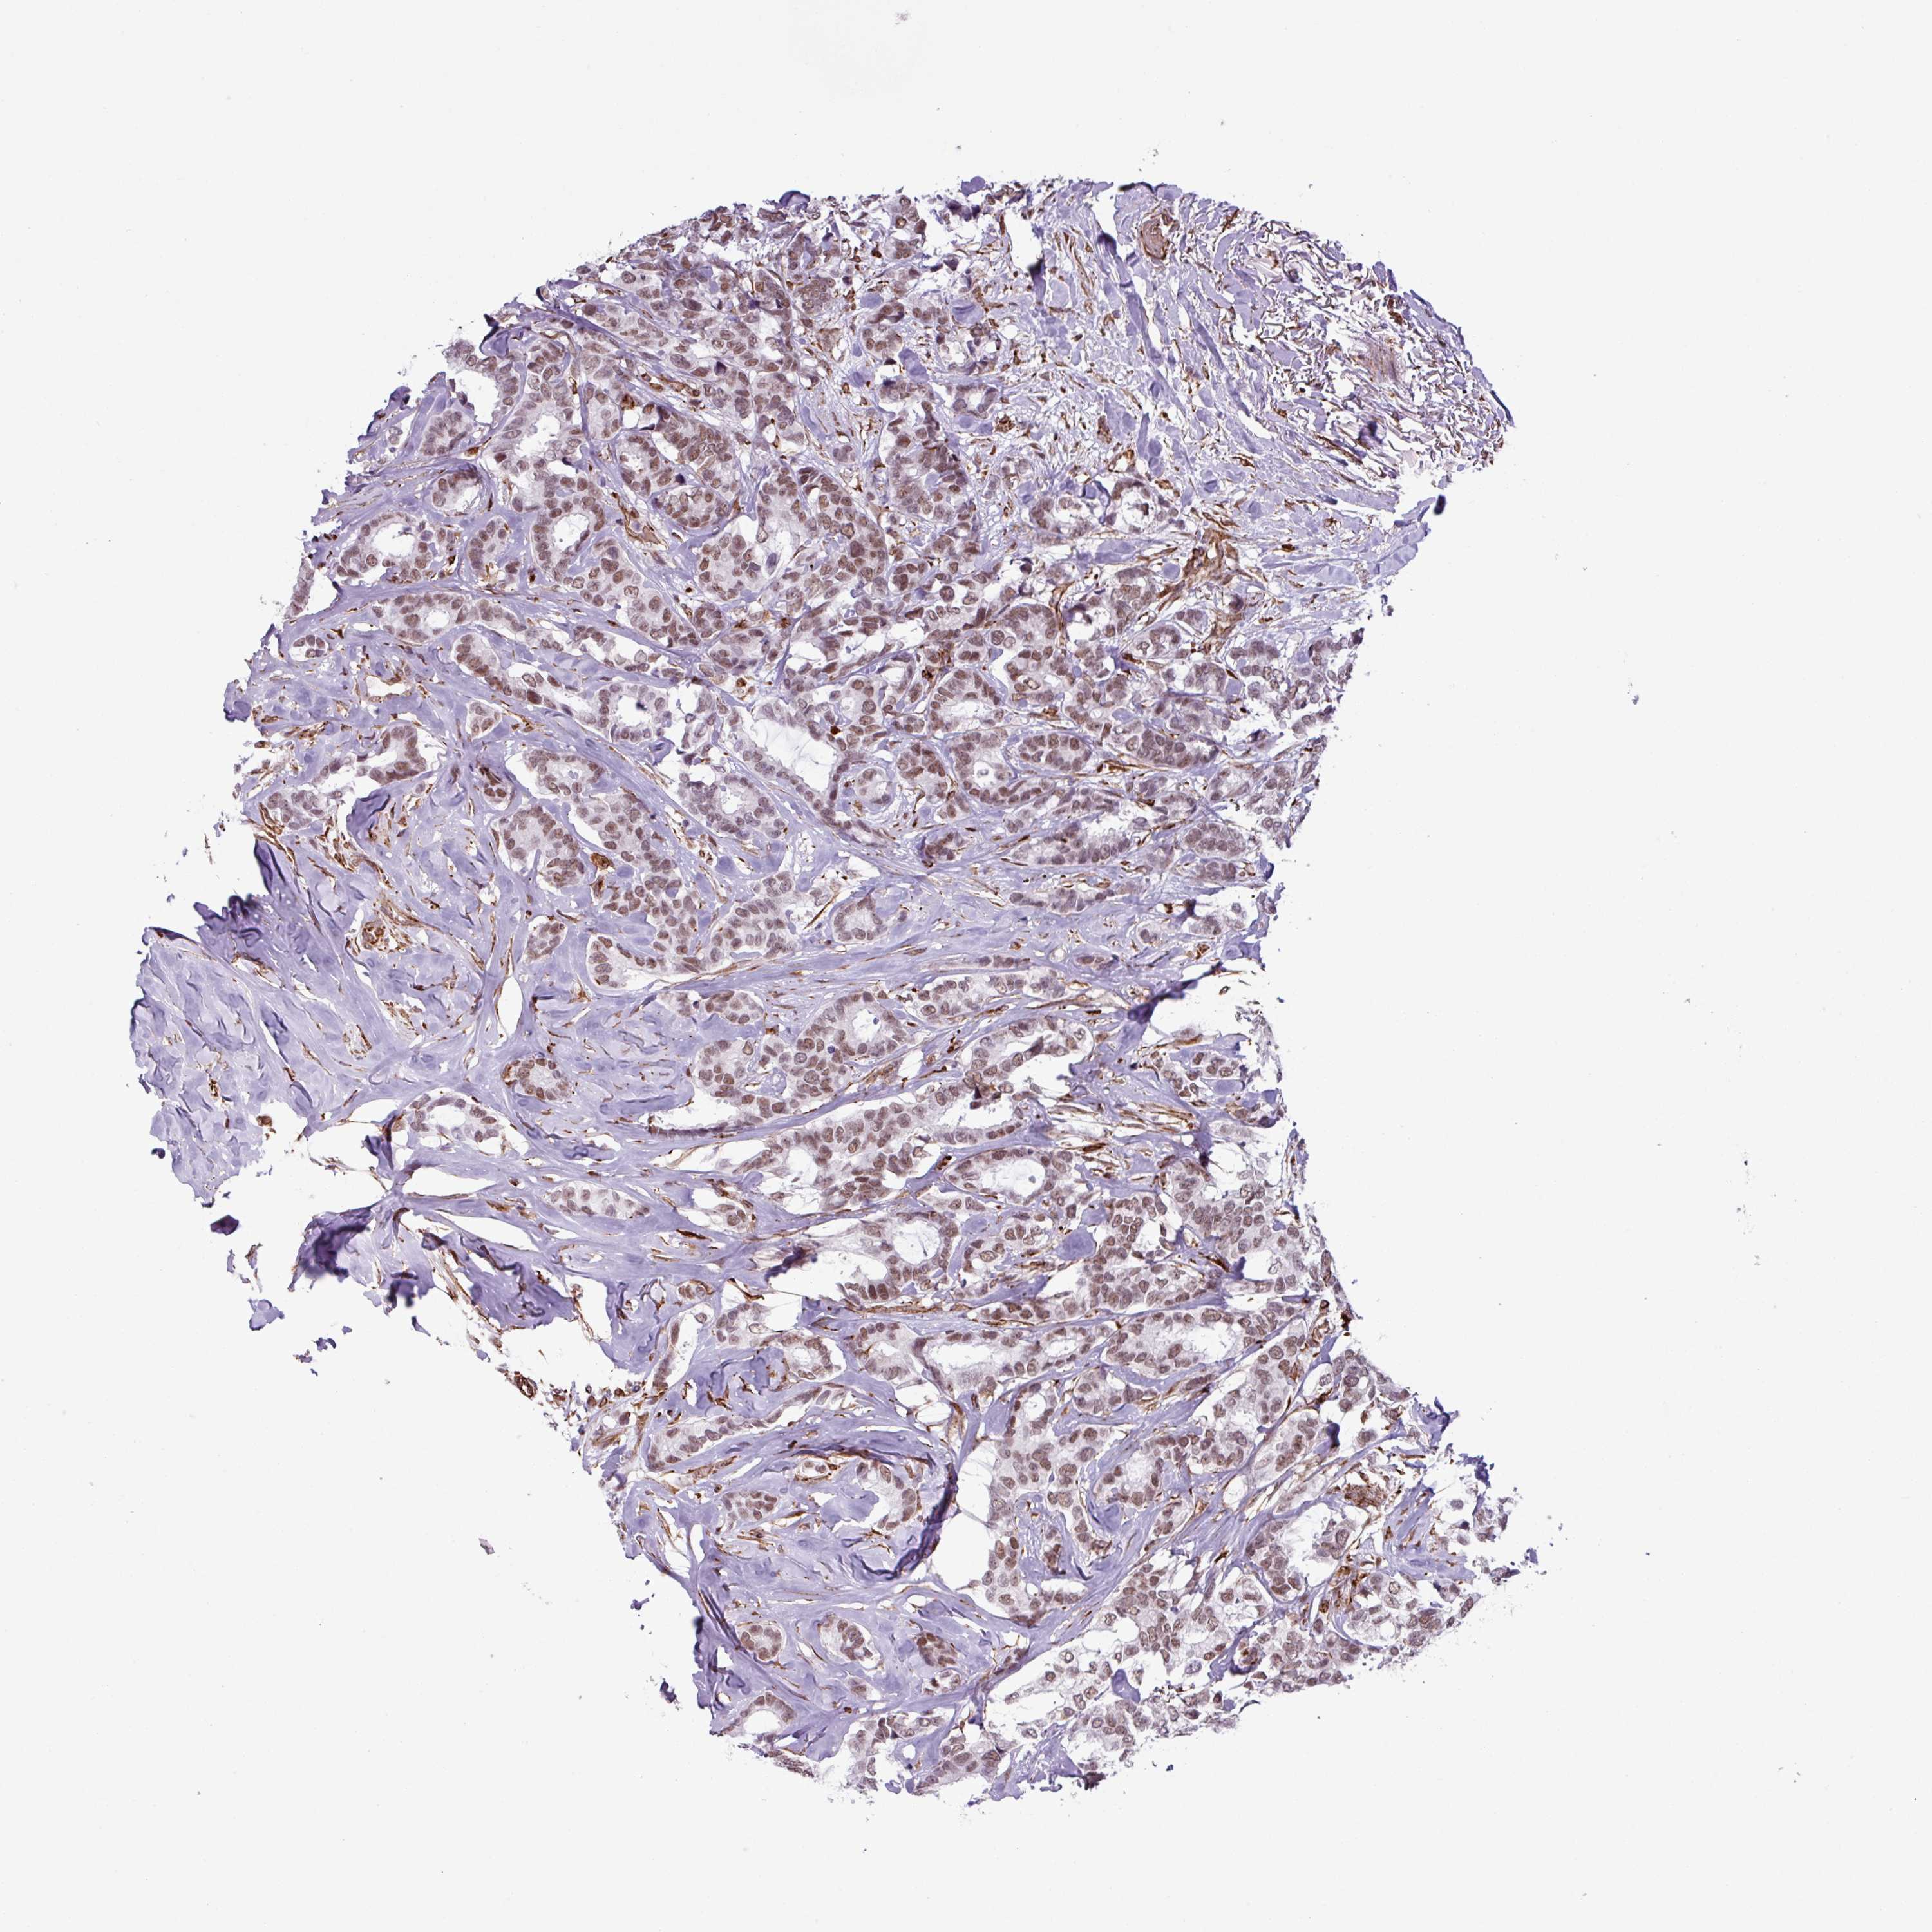

BRCA TCGA BRCA VALIDATION PROTEIN EXPRESSION